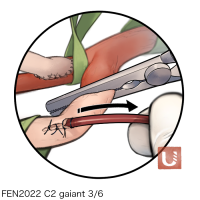

FEN2022シリーズ